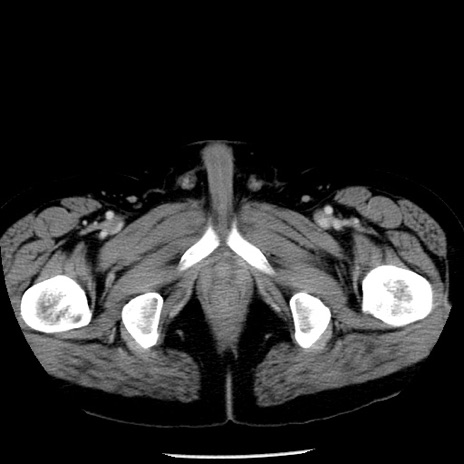

症例29(横断像)

【症例】40歳代男性

【現病歴】2日前から胃痛あり。徐々に周期的な激痛に変化した。本日になっても激痛があるため受診。

【身体所見】意識清明、BT 38-39℃台あり、腹部:膨満、やや硬、右下腹部に圧痛あり。

【データ】WBC 8500、CRP 23.26